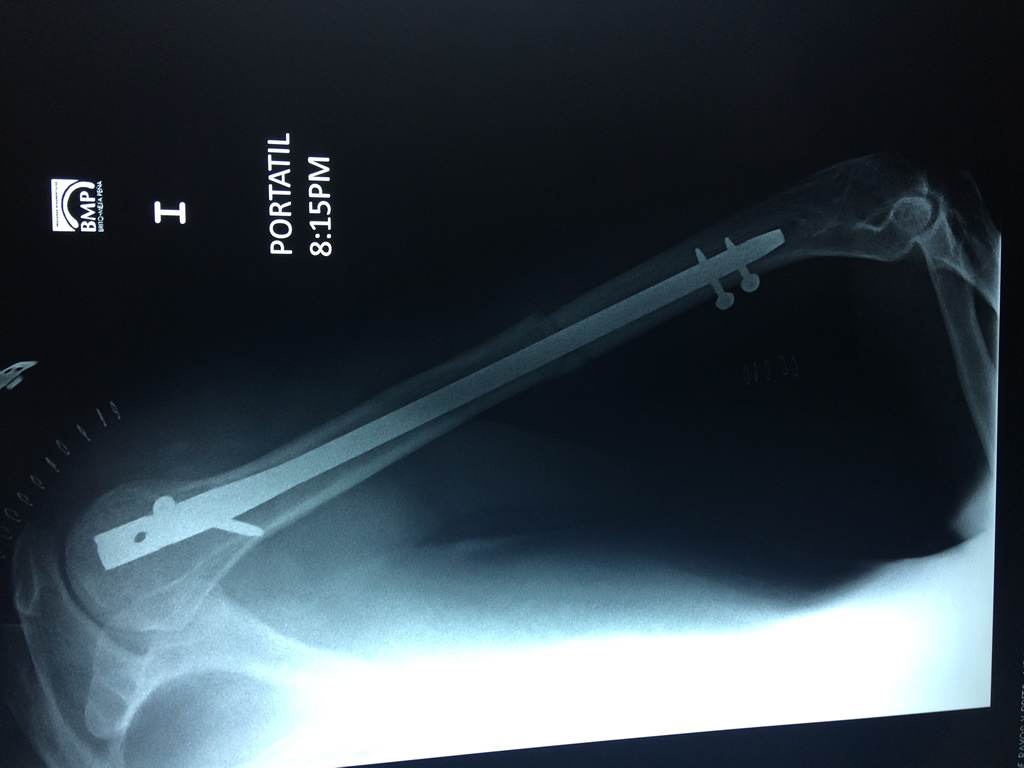

Cirugías de Hombros - Húmero

El Húmero (en latín, humerus) es el hueso más largo de las extremidades superiores en el ser humano. Forma parte del esqueleto apendicular superior y está ubicado en la región del brazo. ... El extremo proximal del húmero tiene la cabeza, cuellos quirúrgico y anatómico y tubérculos mayor y menor.